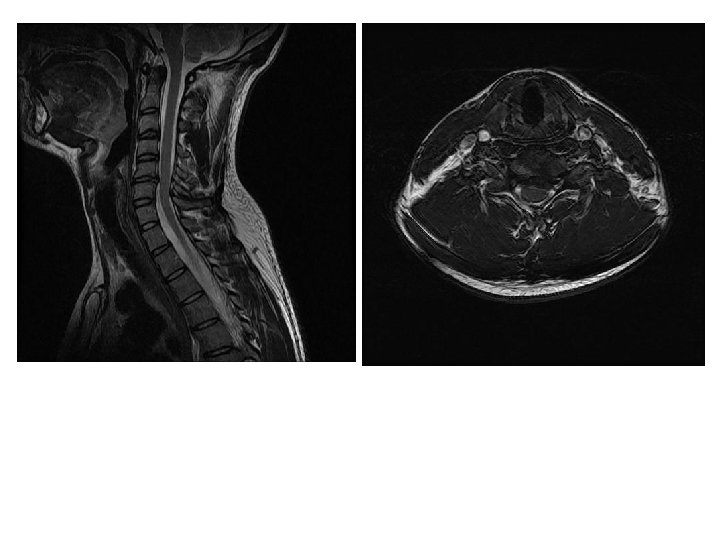

IRM en T 2 coupes sagittales

Cas clinique 2 • Examens complémentaires – EMG confirme l’atteinte neurogène C 6 droite – IRM: discopathie et hernie discale médiane et paramédiane C 5 -C 6 sans modification de courbure cervicale • Propositions de prise en charge?